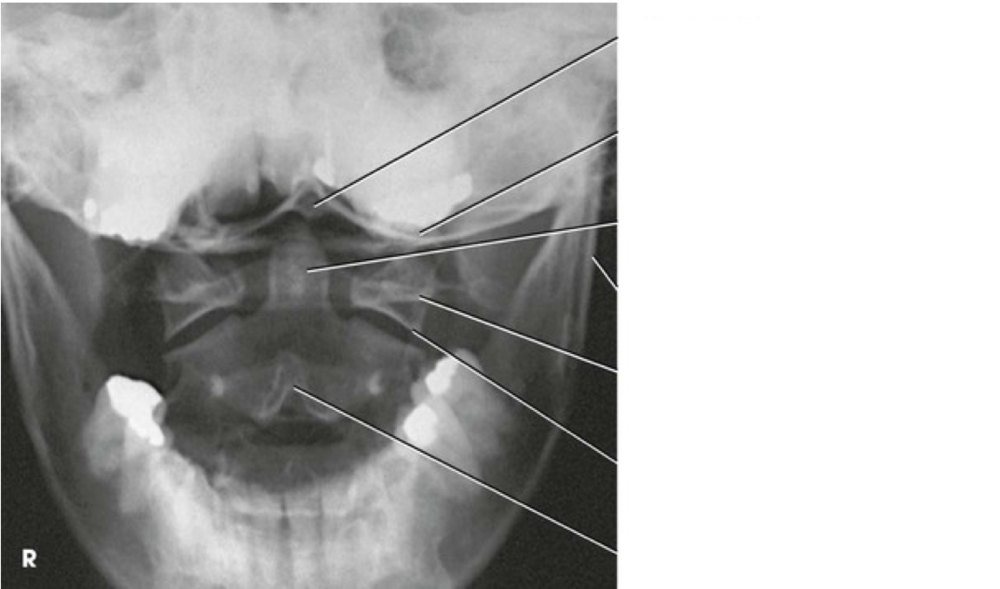

Question 1

Question

Label the image

Image:

Answer

occipital bone

occlusal surface of teeth

dens

mandibular ramus

lateral mass of atlas

inferior articular process of atlas

spinous process of axis